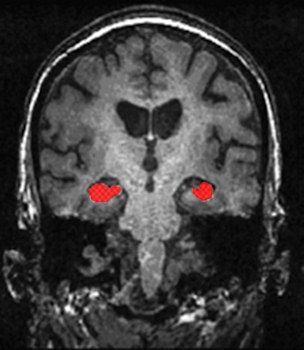

The studies in Rotterdam and similar studies elsewhere have revealed a myriad of results, he added. Notably, that size of the hippocampus is associated with development of Alzheimer's; subjects with smaller or accelerated atrophy rate of the hippocampus are more prone to develop cognitive impairment and Alzheimer's disease.

"We have also found common mutations in the gene sequence of humans that are associated with imaging phenotypes like the volume of the hippocampus. As and when some of these imaging biomarkers, in this case the size of the hippocampus, are validated through large studies, they could become screening tools," he said.